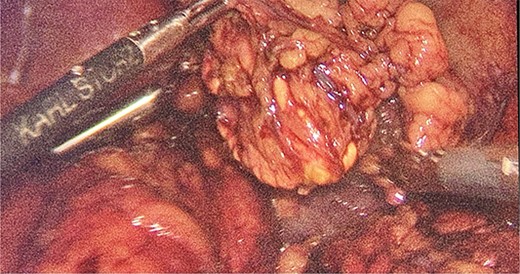

Intraoperatively, the location and resection of the left suprarenal gland (Fig. 2) was found located on the apex of left kidney underneath the body of the pancreas.

We had to first liberate the adhesions of the colon from a previous operation before gaining entry to the left colon. To do so, we made an incision in the White line of Toldt and dissected the right gastrocolic and splenocholic ligaments. This allowed us to access the retrocolic space and approach the left kidney. We identified the left renal vein and the left suprarenal gland and dissected the gland from the fatty tissue of the kidney. The gastrosplenic ligament was also liberated through the ligation of short gastric arteries. After separating the stomach from the posterior abdominal wall, we located the GIST (Fig. 3) on the posterior part of the fundus and removed it through wedge resection (Fig. 4).